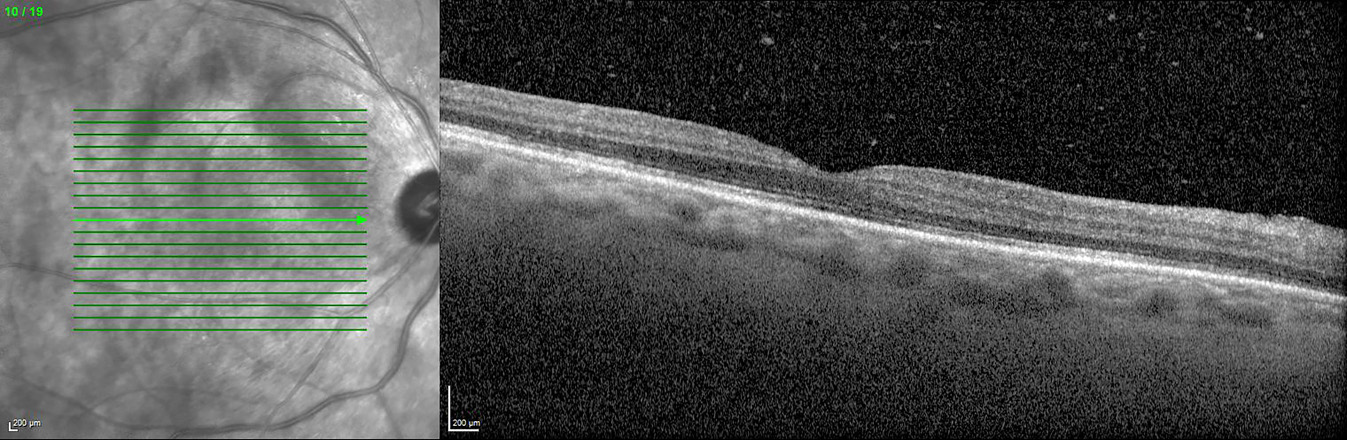

A 57-year-old man from Morocco was referred 109 days after initial presentation for bilateral progressive visual loss and concentric narrowing of visual fields over a period of more than 4 months. Visual loss occurred simultaneously in both eyes, although more severely in the right eye. He experienced photo-aversion and a glare around objects. No previous personal or familial history of ocular complaints was found. Systemic history at presentation: hypovitaminoses D, smoking, surgical inguinal hernia repair. At presentation, best corrected visual acuity (BCVA) using the Early Treatment of Diabetic Retinopathy Study chart (ETDRS-chart) was counting fingers for the right eye and 20/500 for the left eye. Clinical examination demonstrated bilaterally a mild anterior chamber reaction, vitreous opacities (more pronounced in the right eye) and a retinoschisis-like aspect inferiorly with a profound bullous separation of the inner and outer retinal layers. Intra-ocular pressure (IOP) was normal, measuring 10 mmHg in the right and 11 mmHg in the left eye with Goldmann applanation tonometry. Optical coherence tomography (OCT) showed an irregular ellipsoid zone in both eyes with mild loss of the foveal depression in the right eye (Figure 1 [Fig. 1]). Multiple hyperautofluorescent round lesions were visible on fundus autofluorescence (FAF) in the posterior pole (Figure 2 [Fig. 2]). A differential diagnosis of paraneoplastic or non-paraneoplastic autoimmune retinopathy and lymphoma was considered. Vitreal biopsy was considered for laboratory investigation, but due to practical circumstances this was not performed. A full-field electroretinogram (FF-ERG) was performed, which yielded an electronegative response in both eyes (Figure 3 [Fig. 3]), possibly indicating loss of bipolar cell function and photoreceptor function. Clinical findings combined with the electronegative electroretinogram (ERG) made us suspect CAR. Whole-body positron emission tomography-computed tomography (PET-CT) was ordered by the ophthalmologists team and showed accumulation of fluor-18-deoxyglucose (18F-FDG) at the gallbladder, lymphatic nodes near the liver hilus, axial bone(-marrow), pancreatic head, and peritoneally at the right paracolic gutter (Figure 4 [Fig. 4]). These findings suggested a metastasized gallbladder carcinoma, supporting the clinical suspicion of CAR. Cerebral magnetic resonance imaging (MRI) did not reveal any metastatic lesions. A liver endoscopic lymph node puncture biopsy was performed and immunohistochemistry rendered a small cell neuro-endocrine tumor (NET) most likely, with Ki67 40%. Lymphoma was excluded. Because of the CAR-symptoms, a trial of high-dose oral corticosteroids (methylprednisolone 1 mg/kg/day; stepwise dose reduction after 40 days of treatment) was started by the ophthalmological team in consensus with the oncologists. Due to practical arrangements, the multidisciplinary oncological team started palliative chemotherapy with carboplatin-etoposide 10 days after the initiation of oral high-dose corticosteroids. Combined chemo- and oral corticoid-therapy led to the gradual improvement of visual acuity. 18 days after initiation of oral corticoids and 8 days after initiation of chemotherapy the vitreal haze had resolved. At this point attenuated retinal arterioles could be detected. After 4 months of treatment the ETDRS-chart BCVA comprised 20/66 for the right eye and 20/20 for the left eye. Goldmann visual fields became recordable for V4 light stimuli and showed only mild bilateral concentric narrowing of the visual fields (Figure 5 [Fig. 5]). From the oncological point of view, additional immunosuppressive agents were only deemed safe after 4 months into follow-up. To this end, methotrexate was started at a dose of 6x2.50 mg/week, along with folic acid at this moment in time (azathioprine was initially started, but had to be discontinued because it was not supported by the patient). Additional indirect fluorescence in situ hybridization (FISH) showed an autoimmune reaction against retinal antigens in the inner nuclear, outer plexiform and photoreceptor layers (Figure 6 [Fig. 6]). This indicated the presence of anti-retinal autoantibodies and confirmed the diagnosis of CAR. Anti-recoverin antibodies were negative, determination of other different subtypes of anti-retinal antibodies was not performed. Unfortunately, the patient died 9 months after diagnosis secondary to complications of his primary tumor.

Figure 1: Optical coherence tomography (OCT): right eye shows vitreous opacities and slightly irregular ellipsoid zone (also visible in the left eye).